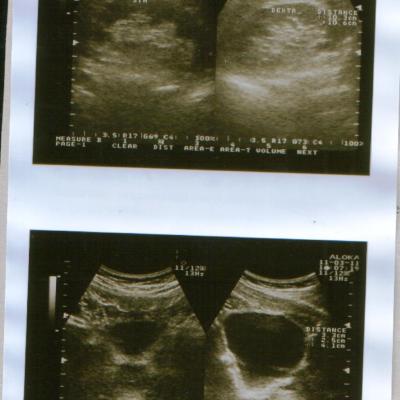

Сегодня(11.03.2011 г.)я ходил на приём к урологу.После осмотра он направил меня на УЗИ мошонки,простаты,мочевого пузыря и почек.УЗИ мошонки показало,что левое яичко действительно сжалось и почти в три раза меньше правого.Уролог сказал,что скорее всего,летняя операция грыжесечения и нынешняя проблема связаны и поставил мне диагноз "Атрофия левого яичка".А,да.УЗИ остальных органов показали,что всё остальное в порядке.Туберкулёза у меня не было и контактов с больными им тоже не было.

Снимки УЗИ и заключение уролога в прикреплённом архиве